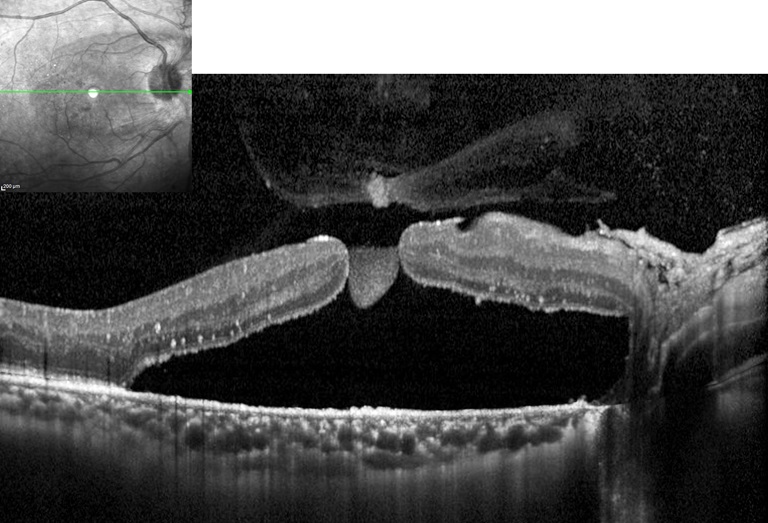

Retinal Detachment with Macular Hole

Presented by Nipan Yodmanee, OD, COAThis photograph received 2nd Place in the category "Optical Coherence Tomography" and was displayed at the 2024 ASCRS/OPS Society Exhibit.